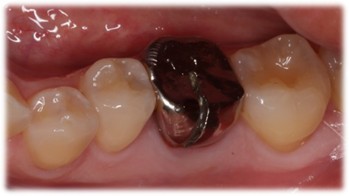

差し歯が入っている歯に痛みが出て他の歯科医院を受診したところ根にひびが入っていて抜歯が必要だということで、セカンドオピニオンで当院に来院されました。

歯を抜かずに残せるのであればそれがベストなので、当院でも冠を外して精査しましたが残念ですが抜歯するしか方法がありませんでした。

即時埋入で対応できることを確認

根の先には根尖病変(虫歯が原因で骨が溶けてしまっている状態)もありましたが、即時埋入で対応することができると判断しました。